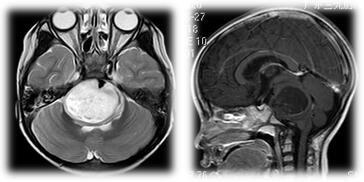

家属代述,2016年3月患儿饮水呛咳,家属未予以重视;5月患儿逐渐出现行走不稳,易摔倒,吞咽困难,伴眼球活动异常。到当地医院就诊,查头颅MRI提示:脑干占位。家属拒绝手术。5月19日转诊至港大医院,患儿左手活动不灵活,行走不能;一周后,患儿精神萎靡,不愿自主活动,因对光反射迟钝,告病重,建议临终关怀。

2016年5月27日,患儿急诊入我院肿瘤综合治疗中心。查MRI:脑干占位性病变,桥脑明显肿胀。ASL:脑干病变内明显低灌注,周围呈等灌注。MRS:Cho峰升高,NAA峰明显减低,Cho/Cr比值1.55,支持肿瘤性病变。